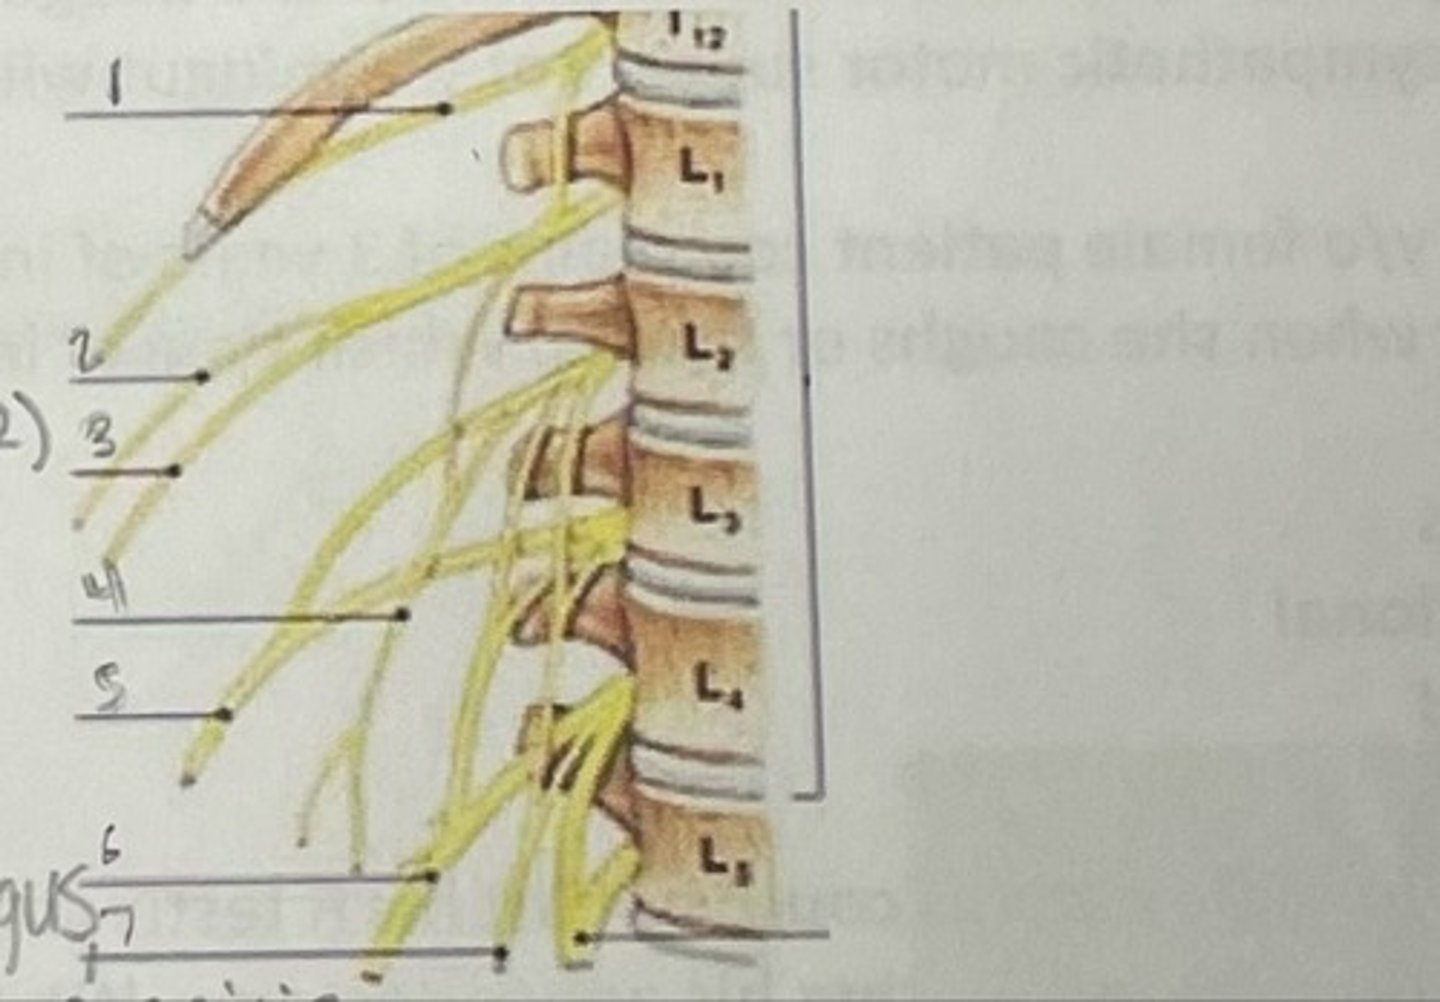

Subcostal nerve (T12)

What is 1

Illiohypogastric nerve (T12/L1)

What is 2

Illioinguinal nerve (L1)

What is 3

Genitofemoral nerve (L1-L2) ; on top of psoas

What is 4

lateral femoral cutaneous nerve (L2-L3)

What is 5

Femoral Nerve (L2-L4)

What is 6

Obturator nerve (L2-L4)

What is 7